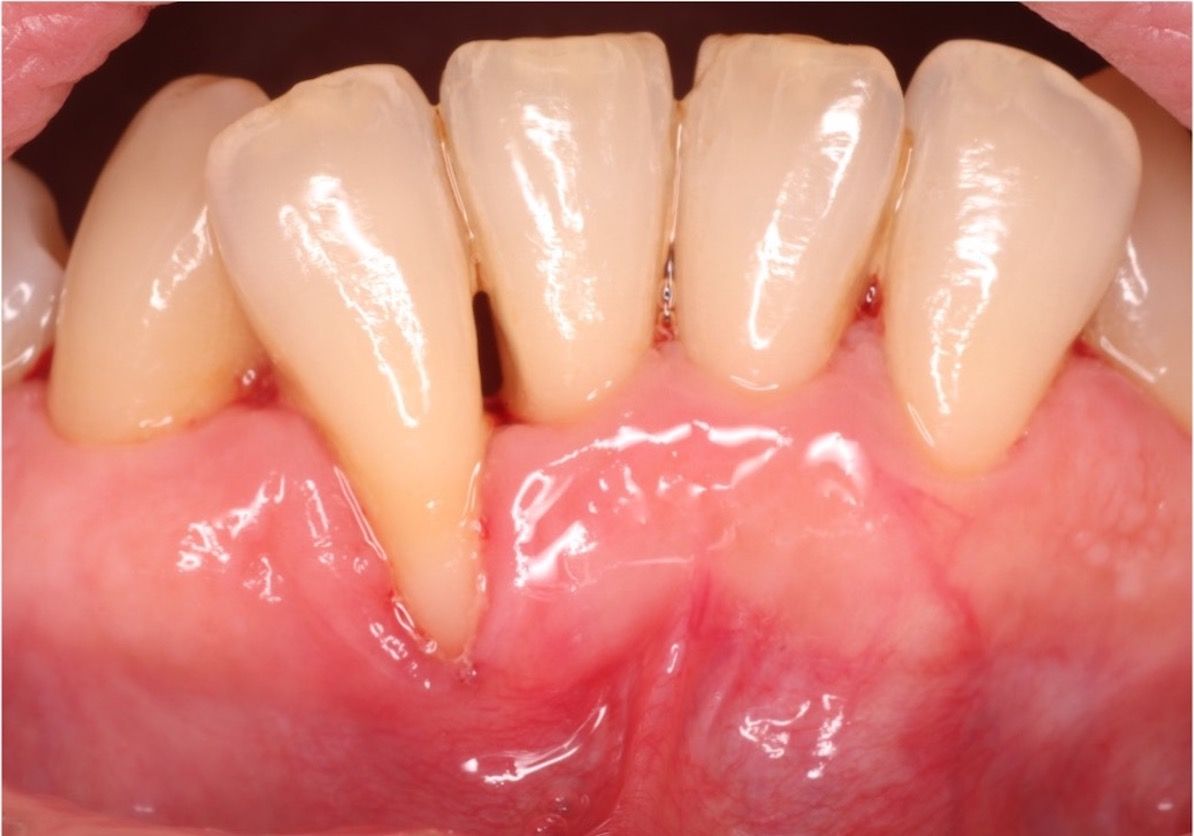

¿TIENES RECESIÓN DE ENCÍAS?

¿Qué es una recesión gingival? La recesión gingival o de encías es una retracción de la encía que deja al descubierto la raíz del diente que anteriormente estaba cubierta por la encía. ¿Por qué se producen? Existen distintas causas, como una técnica de cepillado traumática, el uso de un cepillo duro o incluso la utilización de dentífricos abrasivos, como los blanqueadores. Además, también se pueden provocar por una acumulación excesiva de sarro, prótesis mal ajustadas o incluso por una posición incorrecta de los dientes. ¿Cómo se solucionan? En primer lugar se debe hacer...